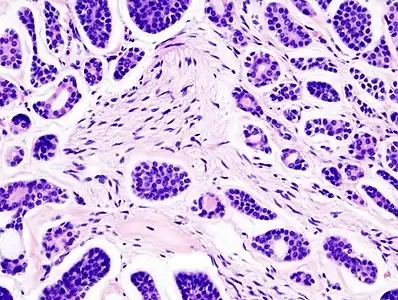

![]() | |

| Micrograph of an adenoid cystic carcinoma of a salivary gland (right of image): Normal serous glands, typical of the parotid gland, are also seen (left of image), H&E stain. | |